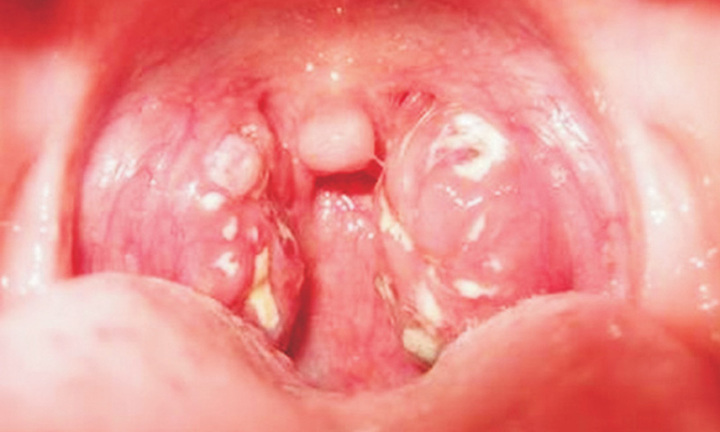

Bé trai 7 tuổi ở huyện miền núi của tỉnh Quảng Ngãi đang được điều trị cách ly vì mắc bệnh bạch hầu.

Bệnh bạch hầu gần như 'biến mất' trong các năm gần đây, tuy nhiên các chuyên gia vẫn cảnh báo nguy cơ mắc căn bệnh nguy hiểm này với các trẻ không được tiêm chủng đầy đủ.